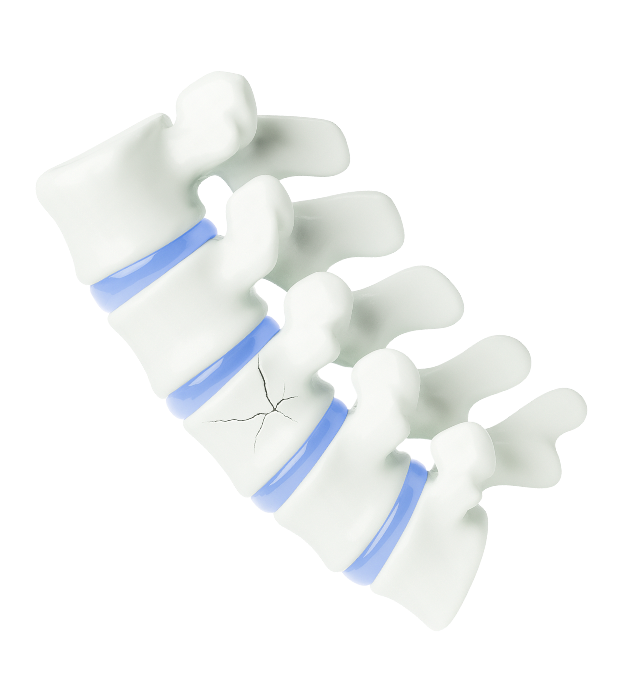

척추압박골절이란?

척추뼈의 앞 부분이 크고 작은 충격에 의해 눌려

납작하게 주저앉아 생긴 골절상태